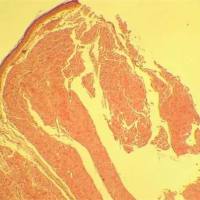

Russell 改良 Movat 五色套染以其染色丰富、鲜艳而大受欢迎。该染色法主要用于显示动脉粥样硬化斑块。Weigert 苏木素 用于染细胞核,藏红品红用于染细胞质,藏红花染胶原组织,阿尔辛蓝染基质(蛋白聚糖)。由于该试剂盒操作过程复杂,其 染色效果跟操作者经验和数量程度有很大关系,所以同时染出十分满意的结果并不容易。

染色结果:

细胞核和弹力纤维 黑色

胶原蛋白和网状纤维 黄色

蛋白聚糖 蓝绿色

类纤维素、纤维素 深红色

心肌平滑肌 红色

泡沫细胞 紫色